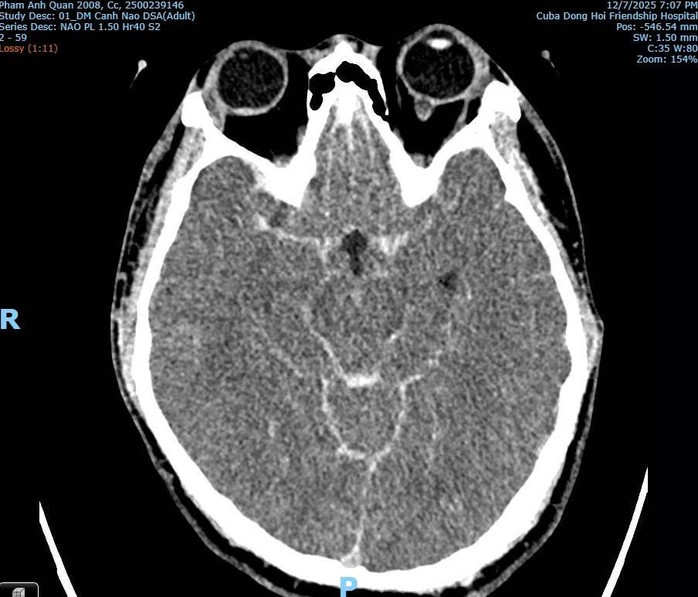

Kết quả hình ảnh CT Scan cho thấy dấu hiệu điển hình của xuất huyết dưới nhện, nạn nhân có thể tử vong do vỡ phình mạch não bẩm sinh, không phải do tác động ngoại lực.

Theo bác sĩ Hùng, hình ảnh chẩn đoán không ghi nhận tổn thương xương cột sống cổ, tổn thương hộp sọ, tổn thương não do lực đánh trực tiếp. Ngược lại, chỉ thấy xuất huyết dưới nhện, phù não lan tỏa, dấu hiệu điển hình của vỡ phình mạch bẩm sinh, không phải chấn thương do bị đánh.

Xuất huyết dưới nhện do vỡ phình mạch máu não của bệnh nhân Q.

Trong clip, sau khi ngã, nạn nhân có biểu hiện co giật, phù hợp với tổn thương não cấp tính. “Đây là đánh giá cá nhân dưới góc độ chuyên môn hình ảnh. Kết luận cuối cùng phải từ giám định pháp y. Tôi mong sự thật được xác định đúng theo căn cứ khoa học” - bác sĩ Hùng nói.